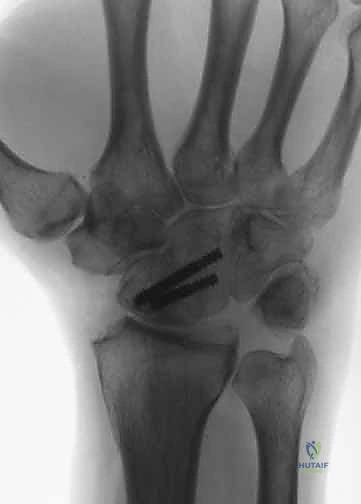

1. دمج الزوايا الأربع (Four-Corner Fusion)

هي العملية الأكثر شيوعاً وشهرة في حالات الانهيار المتقدم (SLAC/SNAC).

* الآلية: يتم استئصال "العظم الزورقي" (Scaphoid) بالكامل لأنه يكون غالباً مصدر المشكلة والألم. بعد ذلك، يتم دمج العظام الأربعة المتبقية في المركز معاً: العظم الهلالي (Lunate)، العظم الكبير (Capitate)، العظم الكلابي (Hamate)، والعظم المثلثي (Triquetrum).

* النتيجة: يتم نقل الحمل الميكانيكي للرسغ من الجانب الزورقي المريض إلى الجانب الهلالي السليم، مما يلغي الألم مع الحفاظ على حركة جيدة للرسغ من خلال المفصل الكعبري الهلالي (Radiolunate joint).